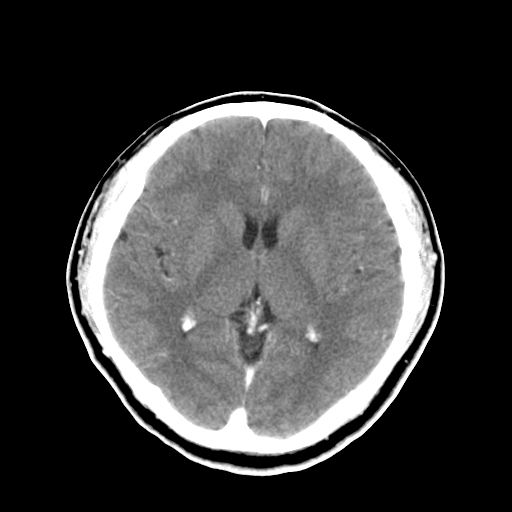

标题: CT16447B:(续)增强扫描图像。 [打印本页]

标题: CT16447B:(续)增强扫描图像。

患者今日做ct增强检查,现补传增强扫描图像。

松果体钙癍增大,无其他改变,定不了性

一般认为大于1cm为异常。